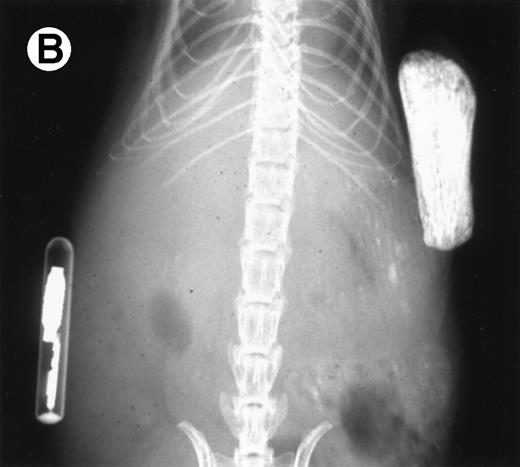

Loss in density of human bone in myeloma-bearing SCID-hu mouse as seen by x-radiography. Human bones are visible in the right-hand side. The highly contrasted devices visible in the bottom left corner are implant transponders used to identify the mice. (A) Myeloma-bearing mouse (patient no. 6): (B) Age-matched control SCID-hu mouse.